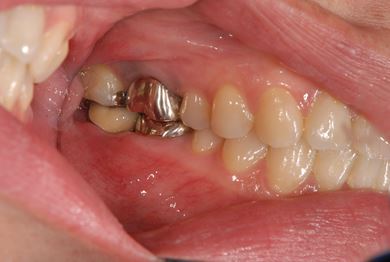

| 性別/年齢 | 女性 / 39歳 | ||||||||||||||||||||||||||||||||

| 主訴 | 右奥歯の虫歯と、右奥のインプラント治療について相談。 | ||||||||||||||||||||||||||||||||

| 治療方針 | 右下奥欠損部分をインプラント治療にて、機能的・審美的回復を行う。 | ||||||||||||||||||||||||||||||||

| 治療内容 | インプラント1本、ハイブリッドセラミッククラウン1本 | ||||||||||||||||||||||||||||||||

| 総治療費 | 329,963円 | ||||||||||||||||||||||||||||||||

| 治療期間 | 5ヶ月 |